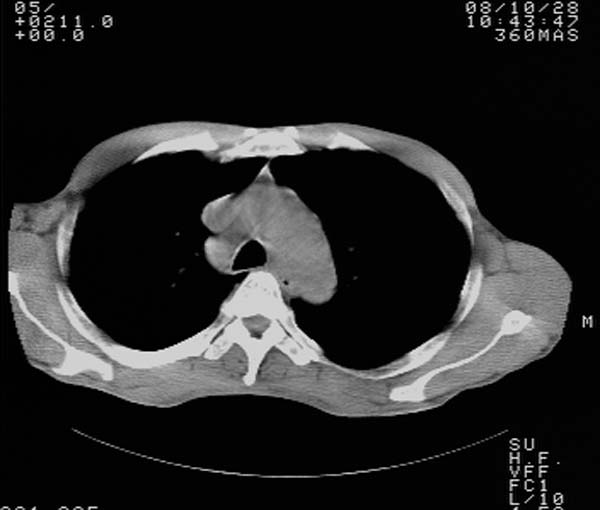

m,65y。半年前发现颈小结节,逐渐增多增大,现双侧耳后、颌下及颈部表浅淋巴肿大。胸片示双肺门增大。外院曾穿刺诊断为淋巴结核。在我科作胸腹部ct,我们觉得外院病检有误。现将图像上传请战友讨论。

纵隔内及腹膜后广泛淋巴结肿大,脾大,肝内似可见低密度影,结合病史半年前发现颈小结节,逐渐增多增大,现双侧耳后、颌下及颈部表浅淋巴肿大。考虑淋巴瘤。

纵隔,双肺门腹膜后多发淋巴结重大,非融合,肝脾轻度肿大,双肺野弥漫性小结节;考虑淋巴瘤,结节病可能性

纵隔内,双肺门、腋窝及腹膜后多发肿大淋巴结影,肺内小结节影,肝脾体积增大,支持淋巴瘤。肝内多发低密度影,考虑小囊肿。

纵隔内,双肺门、腹膜后多发肿大淋巴结影及颈部淋巴结肿大,肝脾体积大.结合临床,淋巴瘤可能性大。